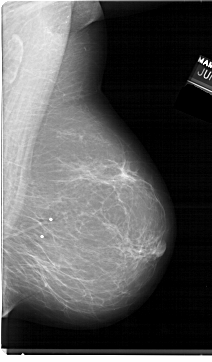

A_1398_1.LEFT_CC

LEFT_CC LINES 6526 PIXELS_PER_LINE 4201 BITS_PER_PIXEL 12 RESOLUTION 43.5 OVERLAY

FILE: A_1398_1.LEFT_CC.OVERLAY

TOTAL_ABNORMALITIES 1

ABNORMALITY 1

LESION_TYPE MASS SHAPE LOBULATED MARGINS CIRCUMSCRIBED

ASSESSMENT 3

SUBTLETY 3

PATHOLOGY BENIGN

TOTAL_OUTLINES 1

BOUNDARY